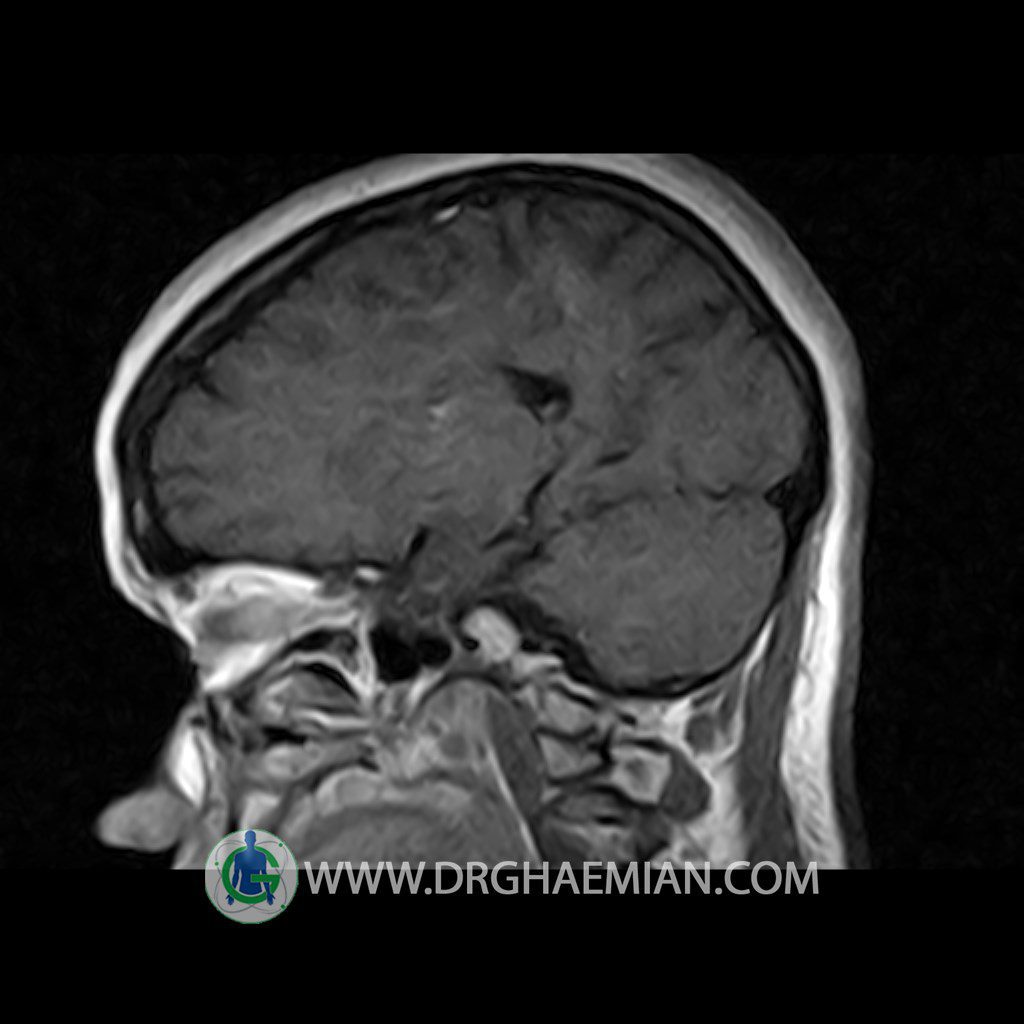

ام آر آی هیپوفیز یک روش تصویر برداری است که از غده هیپوفیز (غده ایی کوچک در مغز که هرومون ها و دیگر غدد بدن را کنترل می کند) و ناحیه های پیرامونش در مغز تصاویری ایجاد می کند. در این کیس سلای نسبتا خالی در ناحیه هیپوفیز بیمار مشاهده می شود.

Technique: Axial , coronal T1 , Axial , coronal , sagittal T2 , Axial, coronal T1 post Gd & 64 dynamic thin coronal slices.

Anterior and posterior pituitary gland were normal .

The sphenoid sinus is clear and pneumatized .

Imaging of the hypothalamus after contrast medium administration was normal.

– Extension of suprasella cistern to sella with thin pituitary gland in floor of sella ( partial empty sella )

is seen